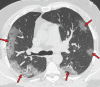

Chest CT has a potential role in the diagnosis, detection of complications, and prognostication of coronavirus disease 2019 (COVID-19). Implementation of appropriate precautionary safety measures, chest CT protocol optimization, and a standardized reporting system based on the pulmonary findings in this disease will enhance the clinical utility of chest CT. However, chest CT examinations may lead to both false-negative and false-positive results. Furthermore, the added value of chest CT in diagnostic decision making is dependent on several dynamic variables, most notably available resources (real-time reverse transcription-polymerase chain reaction [RT-PCR] tests, personal protective equipment, CT scanners, hospital and radiology personnel availability, and isolation room capacity) and the prevalence of both COVID-19 and other diseases with overlapping manifestations at chest CT. Chest CT is valuable to detect both alternative diagnoses and complications of COVID-19 (acute respiratory distress syndrome, pulmonary embolism, and heart failure), while its role for prognostication requires further investigation. The authors describe imaging and managing care of patients with COVID-19, with topics including (a) chest CT protocol, (b) chest CT findings of COVID-19 and its complications, (c) the diagnostic accuracy of chest CT and its role in diagnostic decision making and prognostication, and (d) reporting and communicating chest CT findings. The authors also review other specific topics, including the pathophysiology and clinical manifestations of COVID-19, the World Health Organization case definition, the value of performing RT-PCR tests, and the radiology department and personnel impact related to performing chest CT in COVID-19. ©RSNA, 2020.